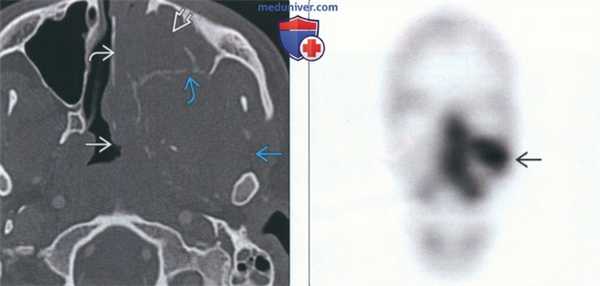

(Слева) На рентгенограмме черепа в боковой проекции у этого же пациента определяется затемнение в области носоглотки, обусловленное объемным образованием.

(Справа) На аксиальной КТ с КУ в мягкотканном окне определяется несколько неоднородная мягкотканная опухоль, занимающая левую верхнечелюстную пазуху и носовую ямку, и распространяющаяся в ветвь нижней челюсти и глотку. Нарушена целостность костной стенки верхнечелюстной пазухи.в) Дифференциальная диагностика саркомы Юинга челюсти:

(Слева) На аксиальной КТ с КУ в костном окне у этого же пациента определяется опухоль с неоднородной структурой, занимающая левую верхнечелюстную пазуху и носовую ямку, распространяющаяся в ветвь нижней челюсти и глотку. Нарушена целостность костной стенки левой верхнечелюстной пазухи.

(Справа) На сцинтиграмме с Тс-99 МДФ у этого же пациента определяется активная фиксация радиофармпрепарата в верхней челюсти слева и носовой ямке в соответствии с локализацией опухоли, обнаруженной на КТ.г) Патология: